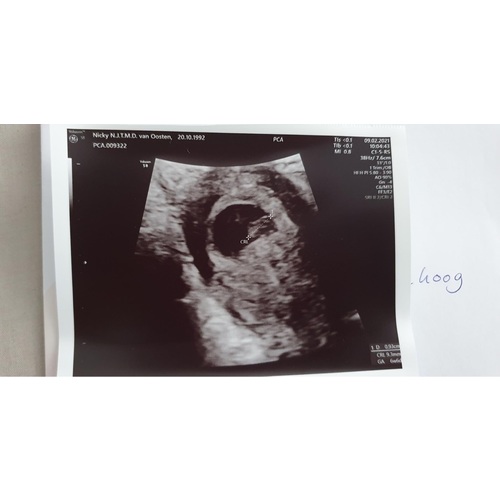

Dit was ons dochtertje met 7+2 weken zwangerschap. Ze was toen 11mm en haar hartje klopte al op een mooi tempo. Veel succes donderdag!